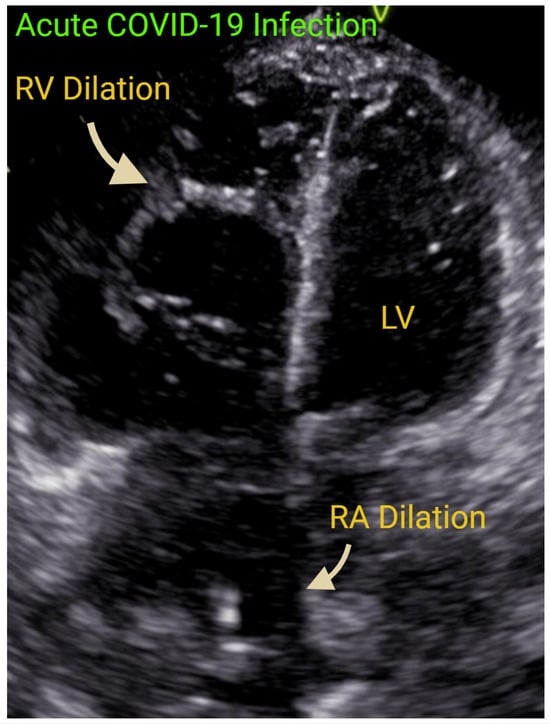

7.1. Acute Right-Sided Heart Failure

- Dandel, M. Heart-lung interactions in COVID-19: Prognostic impact and usefulness of bedside echocardiography for monitoring of the right ventricle involvement. Heart Fail. Rev. 2022, 27, 1325–1339. [Google Scholar] [CrossRef] [PubMed] [PubMed Central]

- Bleakley, C.; Singh, S.; Garfield, B.; Morosin, M.; Surkova, E.; Mandalia, M.S.; Dias, B.; Androulakis, E.; Price, L.C.; McCabe, C.; et al. Right ventricular dysfunction in critically ill COVID-19 ARDS. Int. J. Cardiol. 2021, 327, 251–258. [Google Scholar] [CrossRef] [PubMed] [PubMed Central]

- Shafiabadi Hassani, N.; Shojaee, A.; Khodaprast, Z.; Sepahvandi, R.; Shahrestanaki, E.; Rastad, H. Echocardiographic Features of Cardiac Injury Related to COVID-19 and Their Prognostic Value: A Systematic Review. J. Intensive Care Med. 2021, 36, 500–508. [Google Scholar] [CrossRef] [PubMed]

- Martha, J.W.; Pranata, R.; Wibowo, A.; Lim, M.A. Tricuspid annular plane systolic excursion (TAPSE) measured by echocardiography and mortality in COVID-19: A systematic review and meta-analysis. Int. J. Infect. Dis. 2021, 105, 351–356. [Google Scholar] [CrossRef] [PubMed] [PubMed Central]